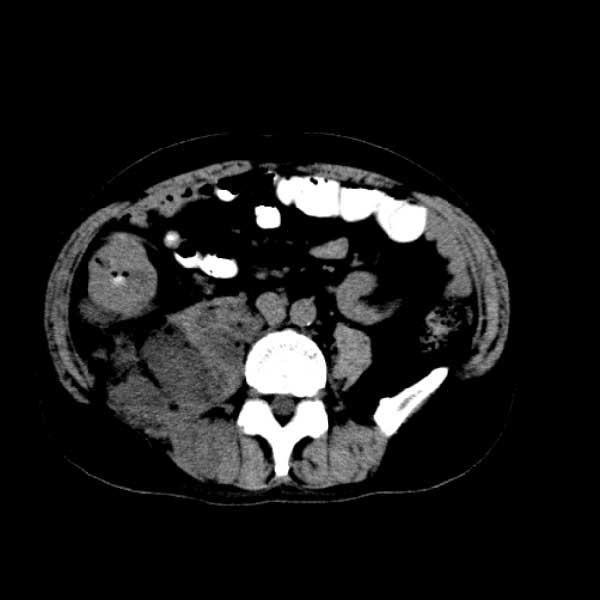

标题: CT13513:男 71 腹部疼痛20余天,近几天高热就诊,骨窗未见异 [打印本页]

标题: CT13513:男 71 腹部疼痛20余天,近几天高热就诊,骨窗未见异

考虑感染性病变可能性大,起源于阑尾?

感染,脓肿形成

考虑为化脓性阑尾炎.脓肿形成.及多肌肉累及.

考虑右侧腰大肌脓肿,向右髂窝、右腹股沟流注。

支持化脓性阑尾炎伴右髂窝脓肿、腰大肌腰方肌脓肿形成。

考虑腹腔及盆腔化脓性炎症,累及右侧髋关节及腹股沟区.

首先考虑化脓性阑尾炎伴腰大肌、腰方肌脓肿,不除外回盲部结核。

回盲部癌待排除。

患者肠镜检查考虑结肠癌,病理证实

患者肠镜检查考虑结肠癌,病理证实。肺部ct可见多发结节,考虑转移